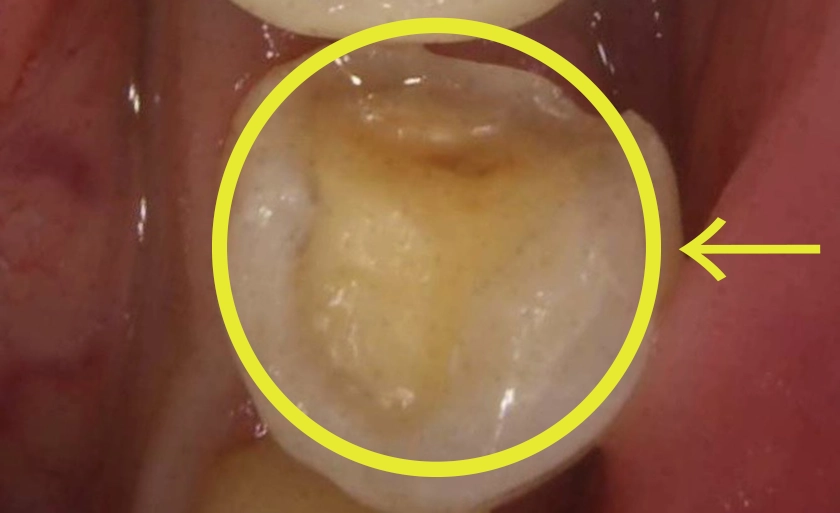

虫歯を削った歯にレジン(複合樹脂)を直接詰める治療法です。保険診療では、15〜30分の限られた時間内で、保険制度で定められた範囲内の基本的な処置のみを行うことになります。

保険診療との具体的な違い

保険診療は接着剤1滴のみ。ダイレクトボンディングは前処理を行い密着力を大幅に向上。